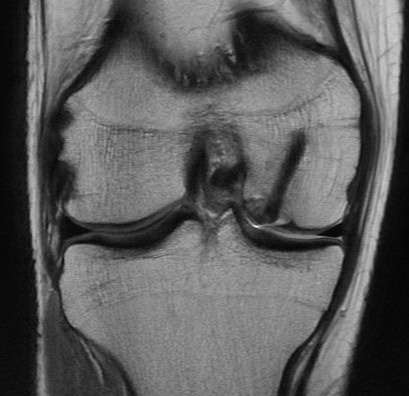

MFC OCD on presentation T2 image 6 months later

T1 sagittal on presentation T1 sagittal six months later